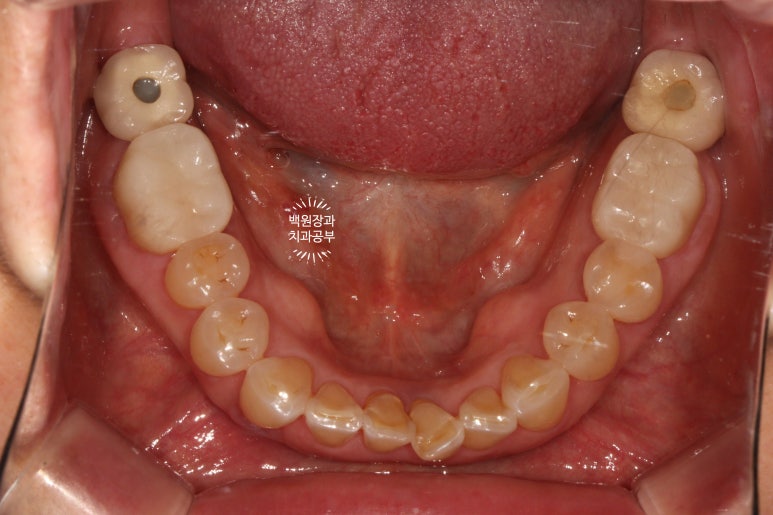

보철물 완성 6개월 후 촬영한 교합면 사진입니다.

특이하게도 좌우 어금니 부위가 맨 뒤의 임플란트 크라운 1개와 지르코니아 크라운 1개가 인접해있는 모양이네요.

지르코니아 크라운은 컴퓨터로 디자인하여 제작하기 때문에, 예로부터 많이 쓰이던 PFM 크라운 혹은 골드 크라운보다 훨씬 자연치아의 모양을 잘 모방하고 있으며 색상도 자연스럽습니다.

주변의 치아들과 상당히 조화로운 색상을 보이고 있고,

그 경계가 잇몸의 경계와 완전히 일치하여 훌륭한 결과를 보여주고 있습니다!!